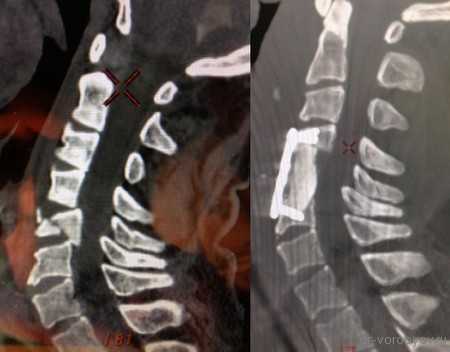

Представлены КТ пациента до и после оперативного лечения по поводу осложненного перелома пятого шейного позвонка. Выполнена корпорэктомия пятого шейного позвонка с комбинированным корпородезом аутокостью из подвздошного гребня и пластиной китайского производства.

На данных томограммах представлен нестабильный перелом тела Тн12 позвонка

Первым этапом выполнена ламинэктомия с транспедикулярной фиксацией китайской системой, а затем проведена корпорэктомия, корпородез аутокостью и тораколюмбальной пластиной китайского производства.